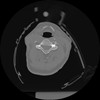

10 P.BLANDAS,,Axial,2.0,P.BLANDAS,,